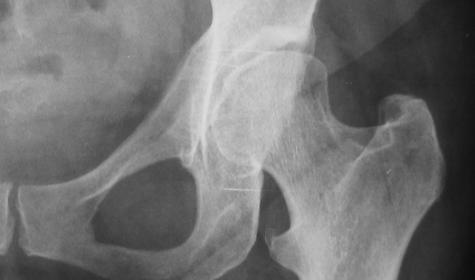

Le fratture del femore sono diventate una delle principali emergenze sanitarie per l’Italia che invecchia. Ogni anno si registrano circa 110 mila nuovi casi, e il dato che più allarma gli specialisti non riguarda solo l’incidenza, ma la sopravvivenza: tra gli over 65, la mortalità a un anno dall’intervento sfiora il 30%. Numeri che fotografano una popolazione fragile, spesso affetta da più patologie e bisognosa di cure complesse, non sempre garantite dai sistemi ospedalieri attuali.

L’aumento delle fratture del femore è legato all’allungamento della vita media e alla maggiore diffusione dell’osteoporosi, una malattia silenziosa che indebolisce le ossa e rende i traumi domestici — spesso semplici cadute — potenzialmente letali. Le conseguenze, però, non sono solo mediche: dopo una frattura, molti anziani non recuperano più la piena autonomia, perdono la capacità di camminare, vengono trasferiti in strutture assistenziali o sviluppano depressione.